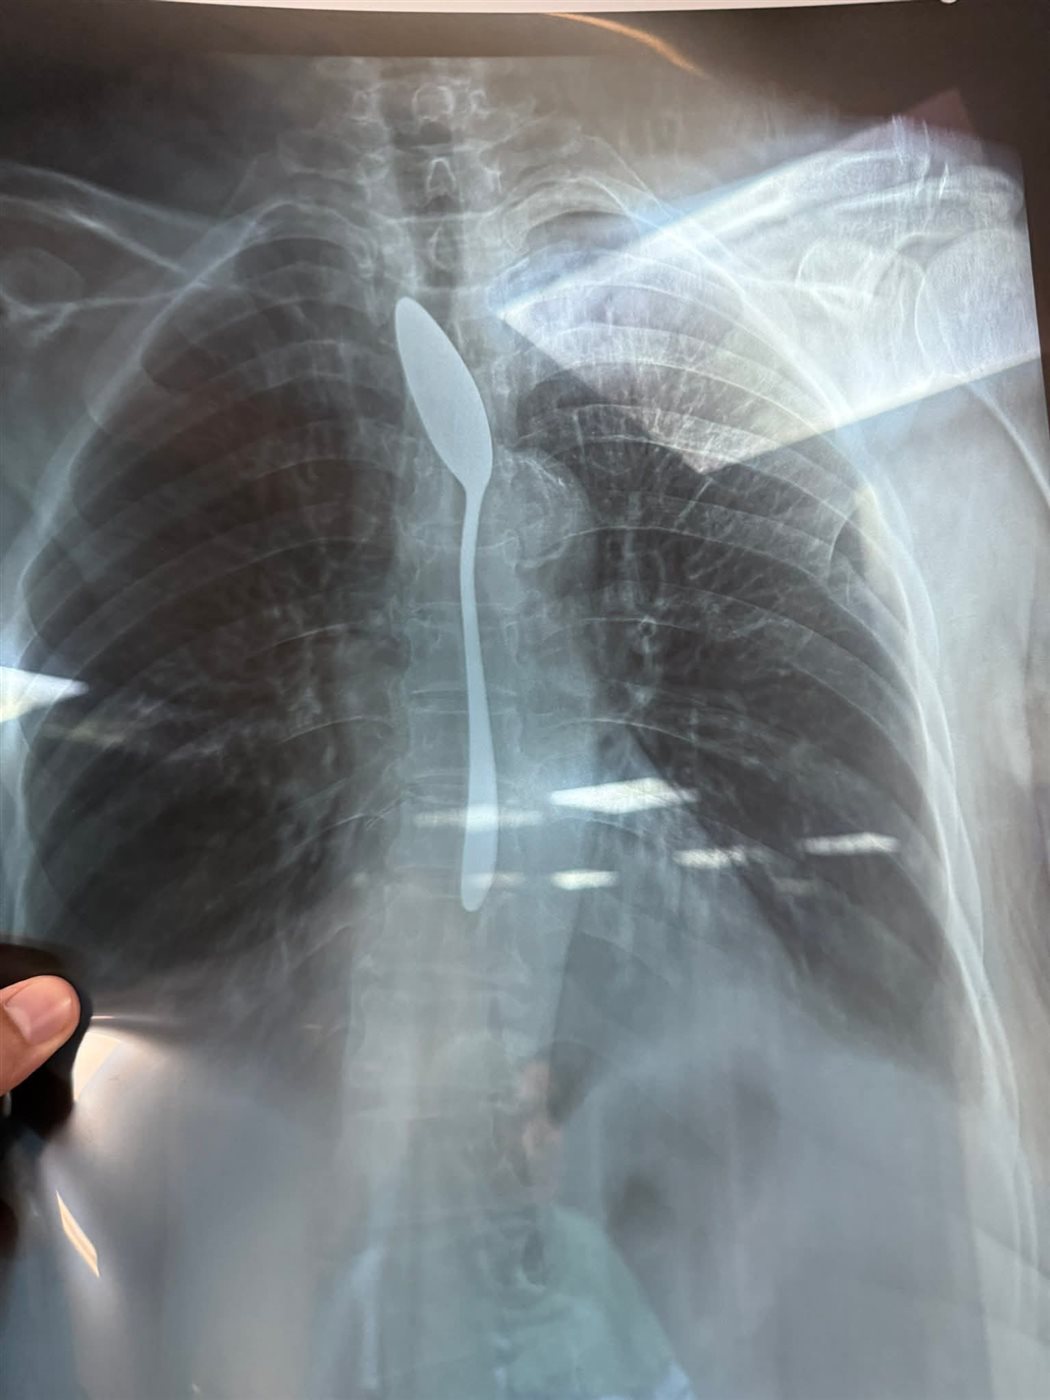

وبحسب مصادر طبية من داخل المستشفى، فقد شك الفريق في صحة الرواية في البداية نظرًا لصعوبة ابتلاع جسم معدني بهذا الحجم لدى سيدة مسنّة، إلا أن نتائج الأشعة أكدت المفاجأة، حيث أظهرت صورة واضحة لملعقة شاي كاملة مستقرة داخل المريء، مما استدعى تدخلا عاجلًا لإنقاذ حياتها.